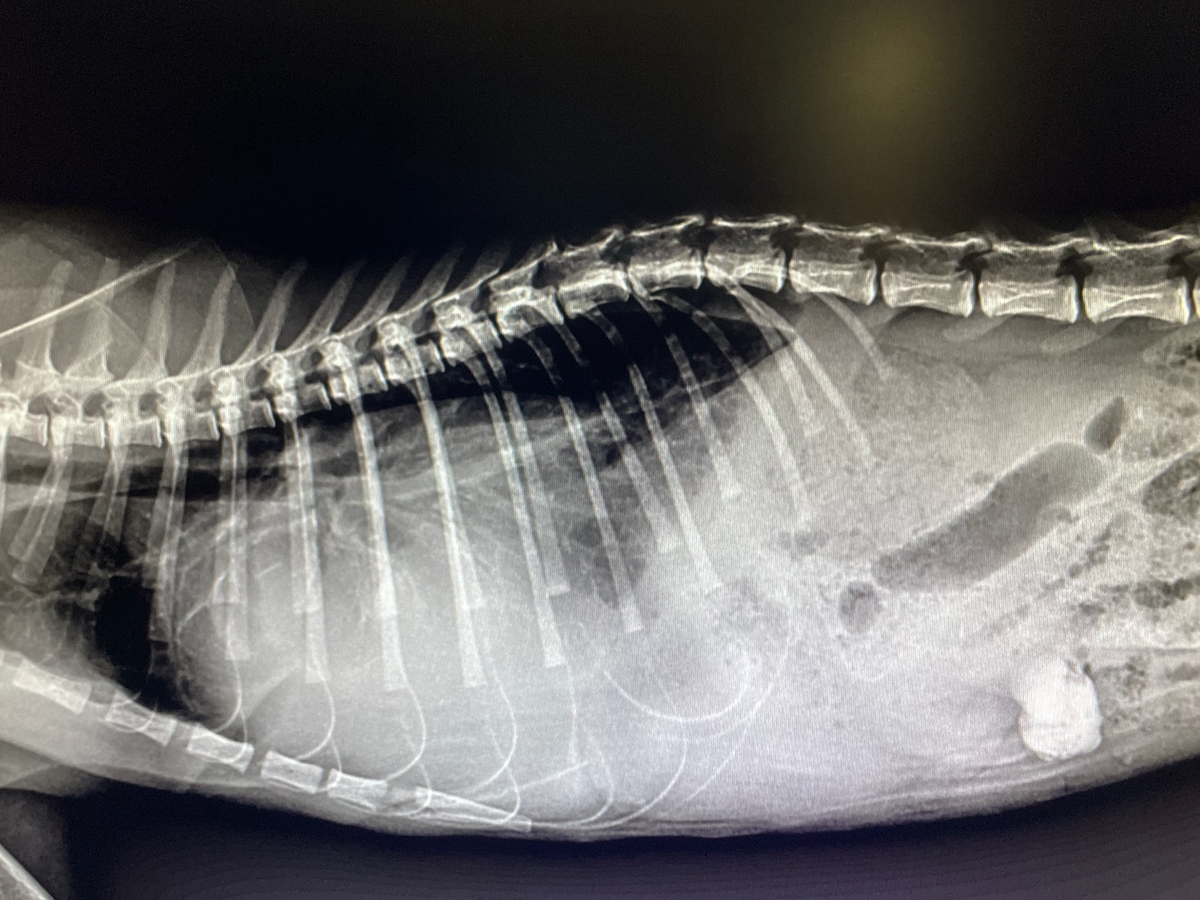

I found this kitten in my yard a few days ago with a mass protruding from the side of her rib cage. I took her to the vet and they said it looked like she was attacked by a larger animal and had matching puncture wounds on both sides of her rib cage. There has been a big rise in raccoon activity in the area lately: Raccoons killing animals so I assume it was a raccoon attack.

One puncture wound resulted in a diaphragmatic hernia that is now it's allowing fluids from other parts of her body to put pressure on her lungs so now she's struggling to breathe and is low on oxygen. After calling around we found a vet with a reasonable surgery fee and even though we don't plan on keeping the kitten we would still like to save her life and find her a forever home.